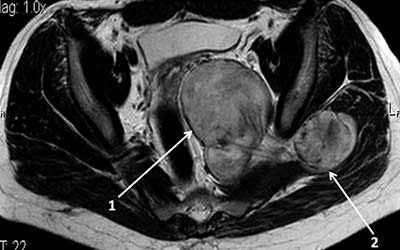

В нейрохирургии ЦЭЛТ работают кандидаты и доктора наук, врачи высшей категории, проводящие научную и практическую работы. Они располагают мощной диагностической базой, позволяющей точно ставить диагноз. Перед тем, как разработать тактику лечения шванномы, они проводят комплексную диагностику, позволяющая установить её размер, локализацию, влияние на окружающие ткани, кистозные изменения. Для этого назначают:

• компьютерную томографию с контрастом;

• церебральную магнитно-резонансную томографию;